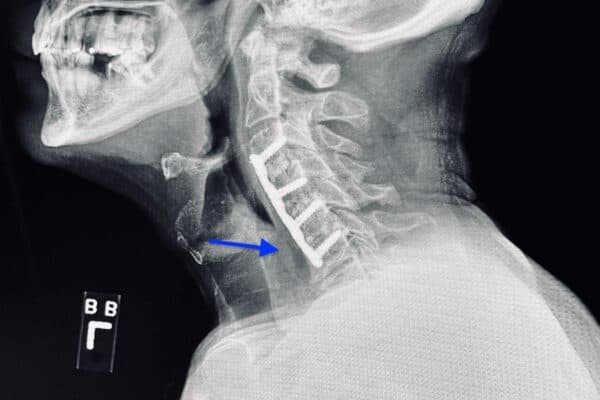

Bác sĩ tiến hành thăm khám để xác định vị trí mắc dị vật chính xác ở trong cổ họng. Phương pháp thường được áp dụng là nội soi, có thể là nội soi ống cứng hoặc ống mềm để theo dõi được sâu bên trong vùng họng của người bệnh.

– Đối với trường hợp dị vật ở sâu thì bác sĩ có thể sử dụng thiết bị nội soi để lấy dị vật ra khỏi vùng họng.

– Đối với trường hợp có tổn thương nghiêm trọng hoặc dị vật cắm sâu vào trong thành họng mà không thể gắp thì có thể sẽ phải can thiệp phẫu thuật.